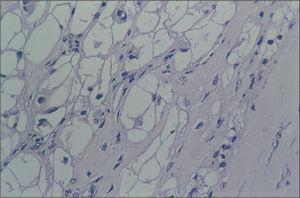

A partir de las 24 h se observan crisis convulsivas clónicas generalizadas con electroencefalograma patológico crisis focal motora en el hemisferio izquierdo con posterior descarga subclínica en el mismo hemisferio que desaparece con diazepam, fenobarbital y anticonvulsivantes. Actividad de fondo deprimida. En los controles posteriores se observan dos descargas irritativas subclínicas en región frontal en forma de onda lenta regular de unos segundos de duración, y otra de onda lenta aguda en región temporal. Extubación a los 4 días. A los 10 días se realiza tomografía computarizada craneal: en zona subependimaria lesión puntiforme en posición posterior del asta frontal del ventrículo derecho lateral derecho por encima del agujero de Monro, que pudiera corresponder a un pequeño hamartoma. Hipodensidad bilateral y simétrica en la zona posterior de los lóbulos temporal, occipital y parietal. Se produjo hemorragia parietal que le provocó ceguera cortical que cedió 10 meses después. A partir de los 18 días el EEG fue normal. El ecocardiograma mostraba ausencia de tumor en la zona subaórtica. Válvula aórtica normal. El eco-Doppler reveló gradiente máximo en el tracto de salida del ventrículo izquierdo de 16 mmHg. En el estudio anatomopatológico microscópico se encontraron células en araña con masa citoplasmática central y núcleos excéntricos. Imágenes radiales hasta la periferia (fig. 2). Los citoplasmas contenían gránulos de glucógeno y la masa citoplasmática contiene mitocondrias, miofibrillas y septofibrillas con bandas en Z. Fue dado de alta un año después de la intervención.

Figura 2. Células en araña con masa citoplasmática central y núcleos excéntricos. Imágenes radiales hasta la periferia.